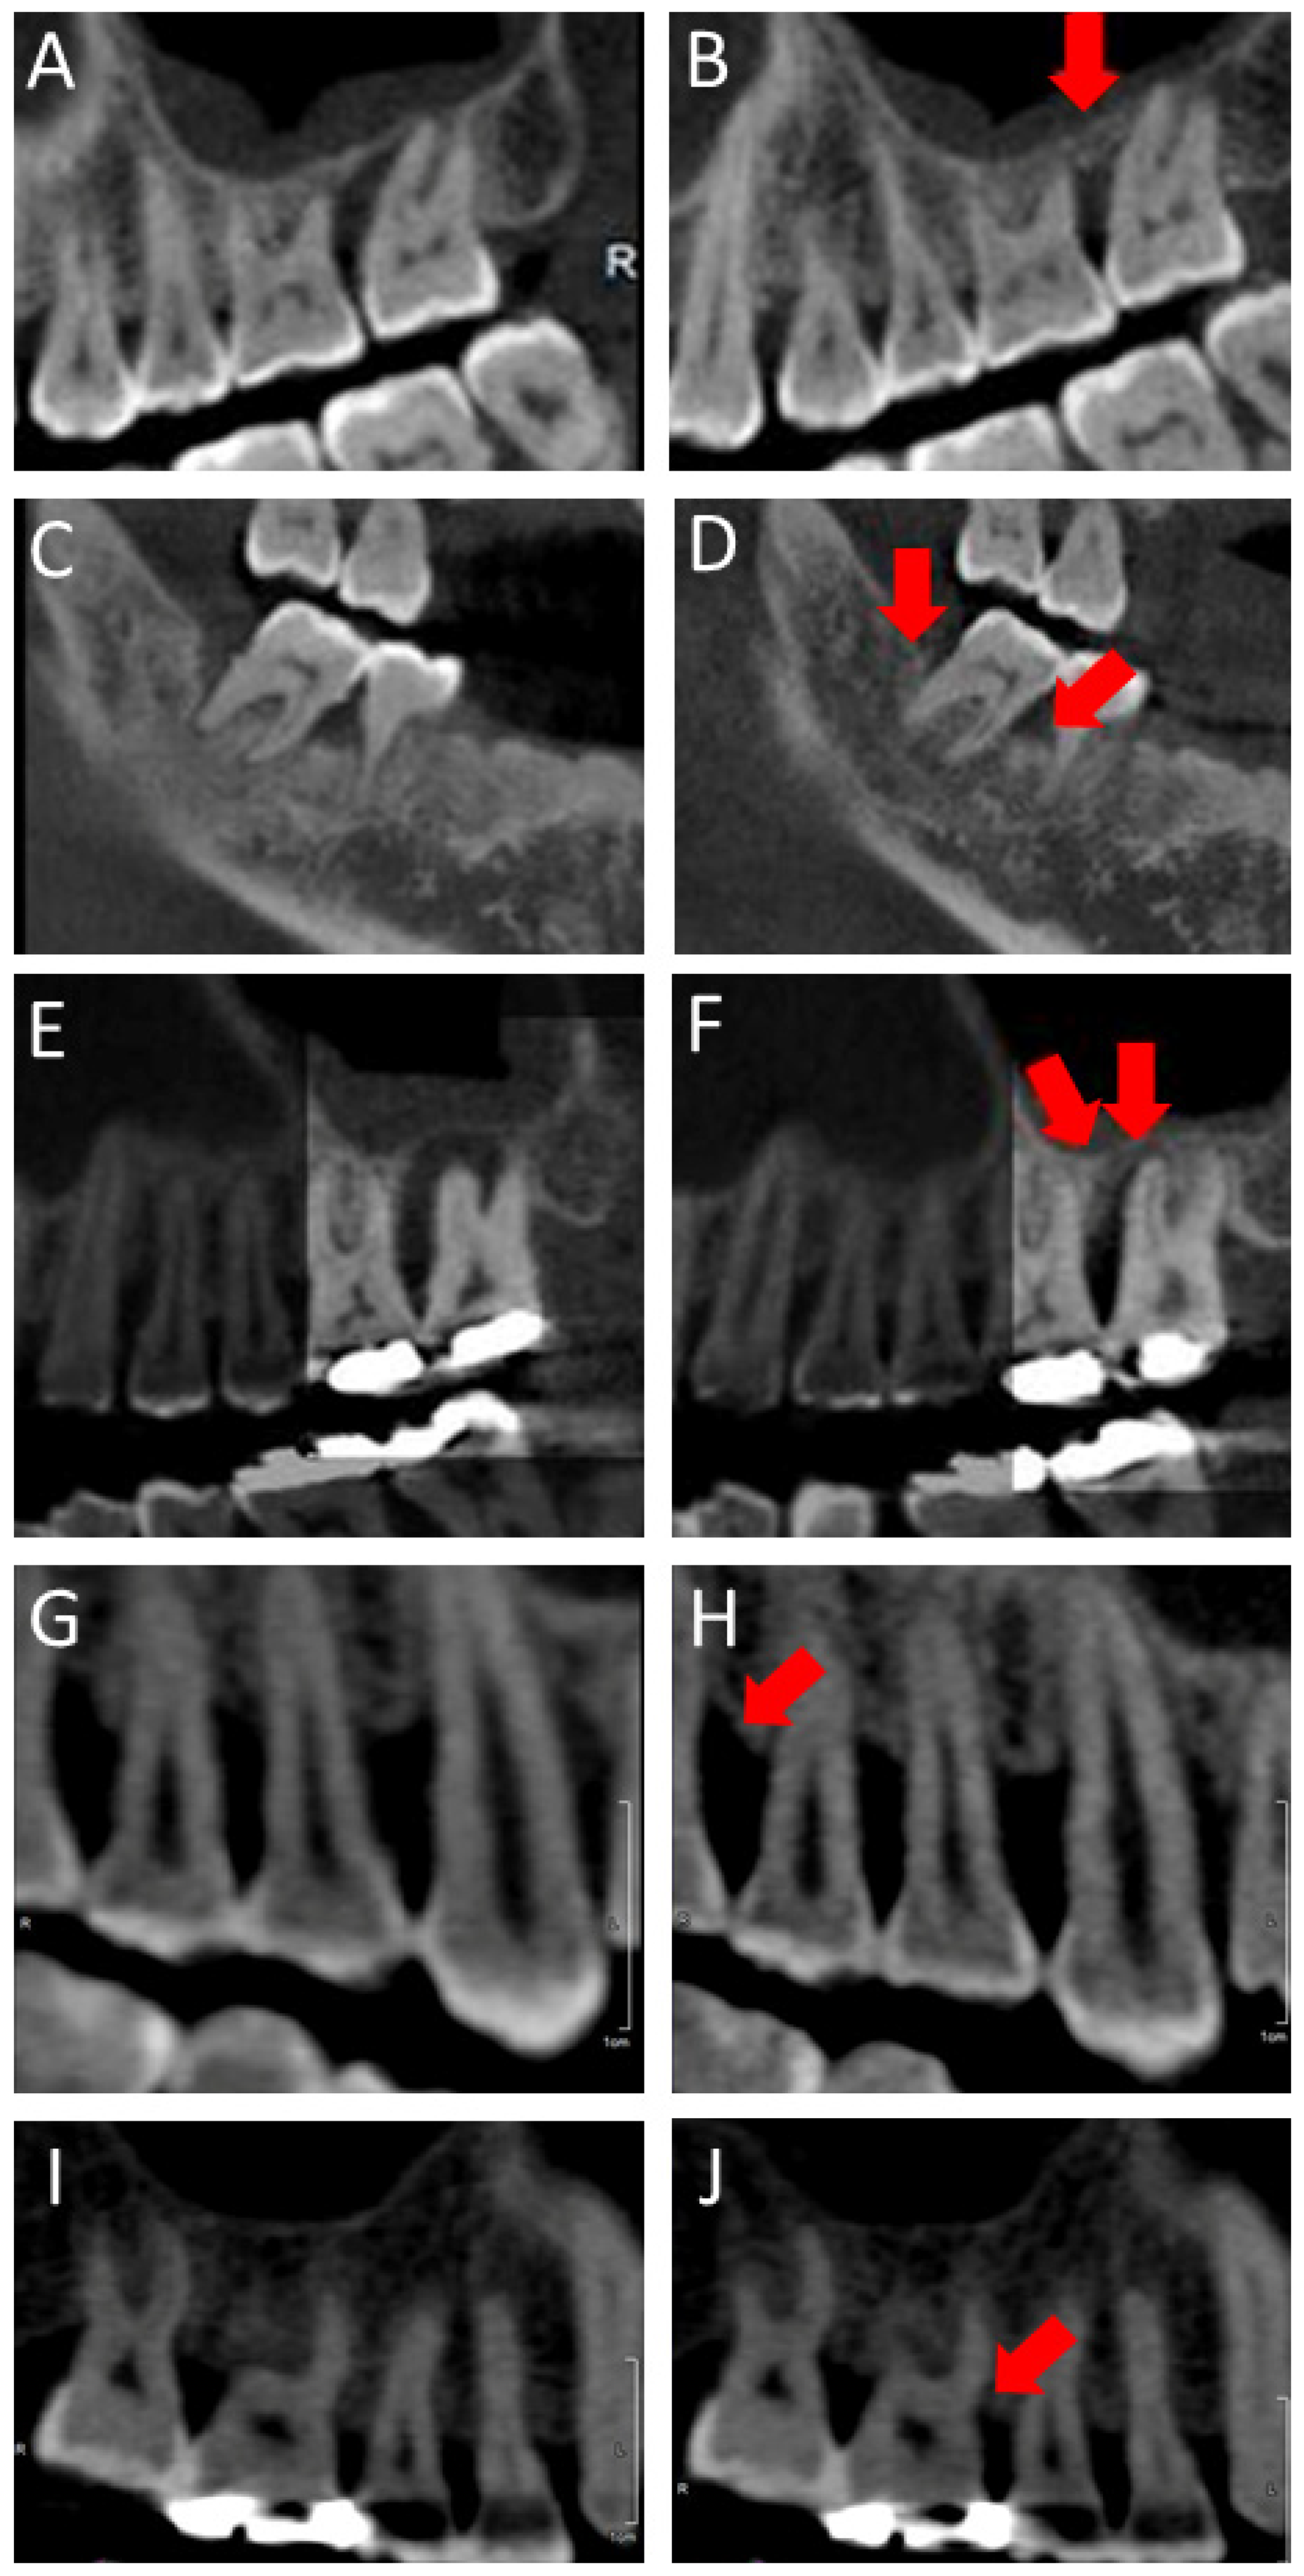

2.5. Radiographic Evaluation and Bone Height Measurement